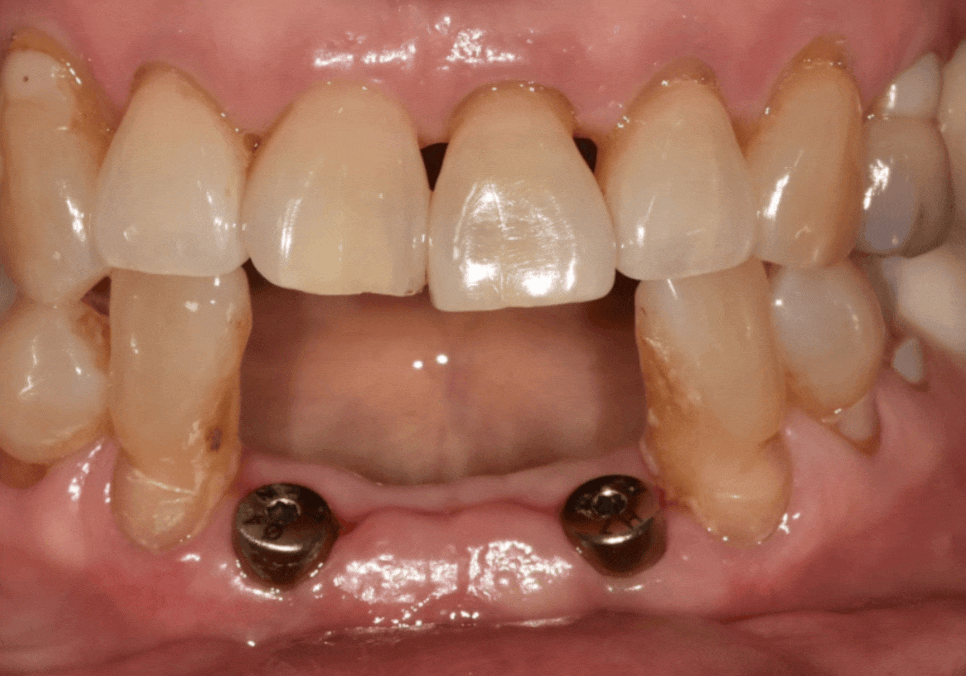

결국, 앞니 4개를 모두 발치하고

임플란트를 진행했습니다.

251230

오랜 염증으로 잇몸뼈가 많이 내려가 있는 상태라,

일반적인 보철물을 올리면

치아가 비정상적으로 길어 보여

인상이 어색해질 우려가 컸는데요~

치아가 길어지지 않게

핑크 포세린(잇몸 색 도자기)으로

잇몸을 재현하여

260116

치아 길이가 짧아 보이도록

제작했습니다.

잇몸뼈가 많이 소실된 상황이었지만,

치아의 비율을 세심하게 조정한 덕분에 어색함 없이 아주 자연스러운 결과가 나왔습니다.^^

251022 (전) 260116(후)